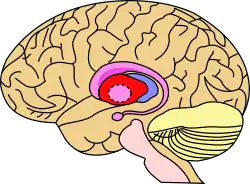

Putamen (in red) shown within the brain